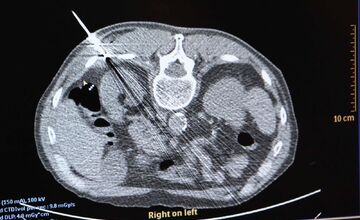

FOTO: Košická univerzitná nemocnica zaviedla pokrokovú liečbu tumorov

VIDEO: Nová nádej pre onkologických pacientov: Unikátna metóda zničí nádor mrazom, využívajú ju aj v Košiciach